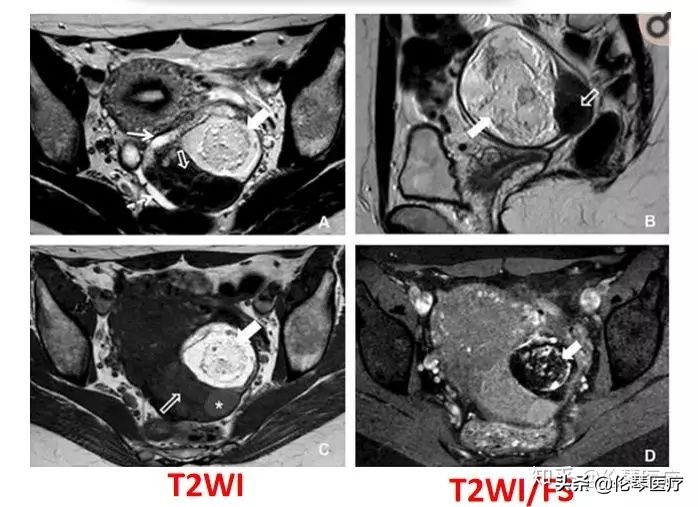

如图所示是卵巢肿瘤中一种比较常见的畸胎瘤,它含脂肪和牙齿,脂肪组织在磁共振常规序列上呈现为高信号,通过抑脂成像,脂肪信号下降,很容易分辨出肿瘤内含有脂肪。

磁共振增强扫描,可以看到是否有特别的软组织强化,如果没有就是良性的畸胎瘤,如果有增厚的、结节样的肿块,有软组织成分强化,就要考虑是恶性的畸胎瘤。

如图所示是卵巢肿瘤中另一种比较常见的实性肿瘤——卵泡膜纤维瘤,在绝经后妇女中发病率比较高。卵泡膜纤维瘤是一种良性肿瘤,如果术前能够很清楚地诊断出来,对患者的预后和心理都非常有帮助。磁共振在这方面,非常有价值。卵泡膜纤维瘤里含有大量纤维组织,这些纤维组织在CT和超声上,都没有特异性,分辨不出来,但在磁共振上,T2WI表现为低信号,非常有特征性,很容易就能得出诊断。